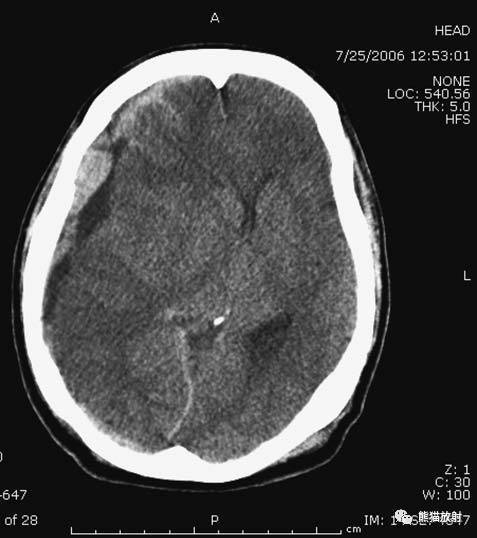

蛛网膜下腔出血还是小脑幕硬膜下血肿? | 医学影像园

(小脑幕下)硬膜下血肿.